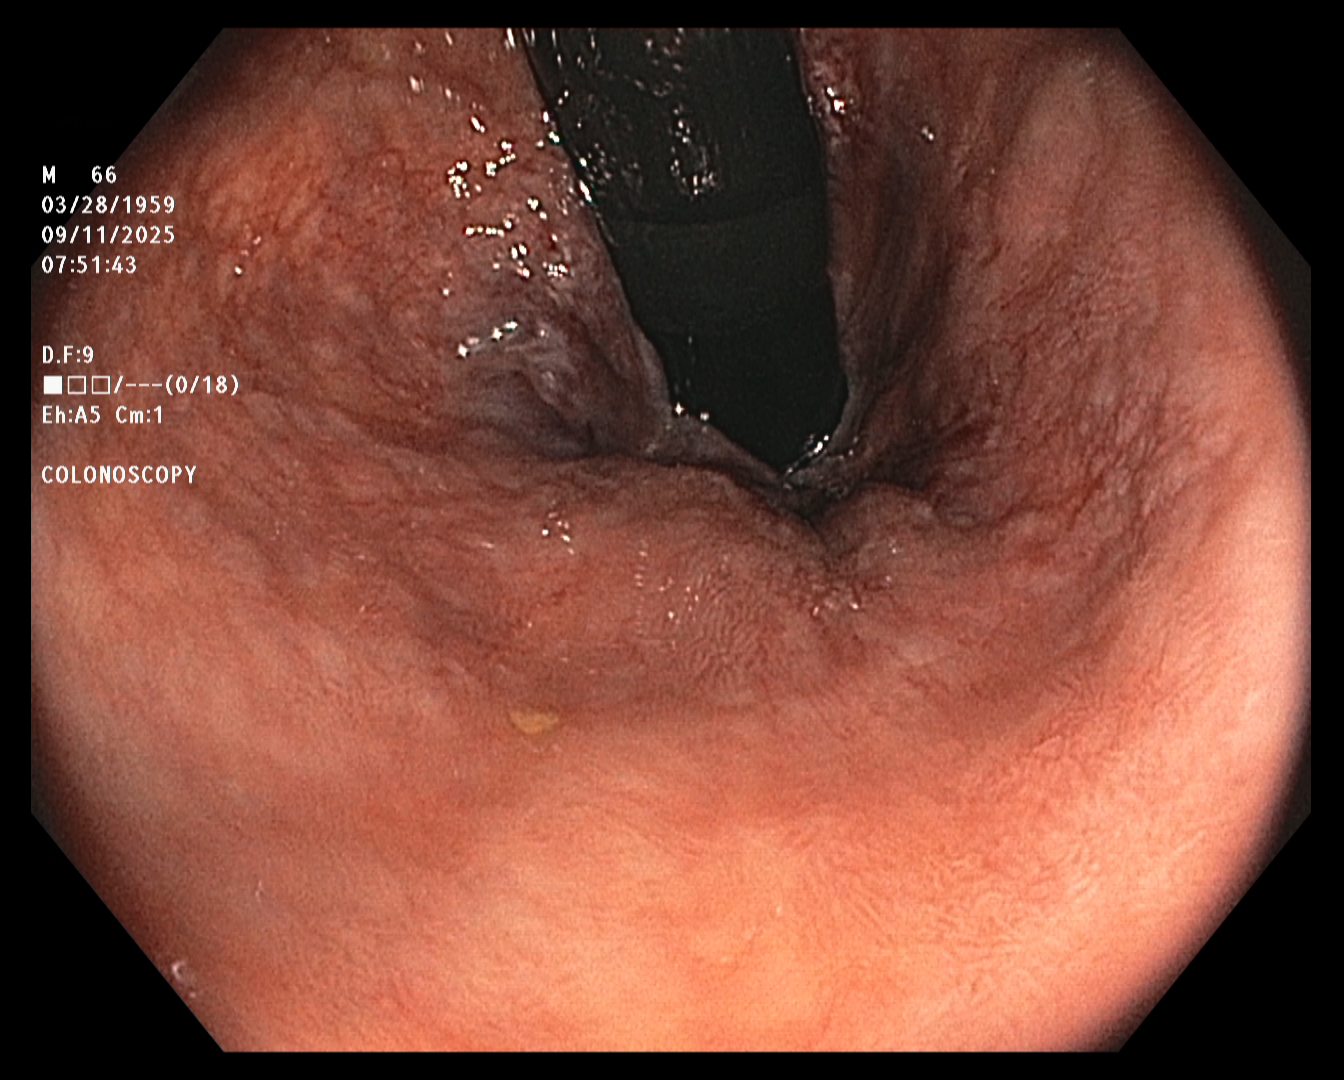

The endoscopist in this study generated a series of images showing the cecum and several sites

of concern (e.g., polyps). The cecum is the beginning of the colon, so reaching it ensures that

the entire colon will be examined. The endoscope was slowly withdrawn, while the endoscopist

assayed mucosal detail and identified and removed several polyps for later examination. The

first and last images were taken about twenty minutes apart.

The colonoscopy results were relatively unconcerning. However, because polyps were

detected, the patient was advised to repeat the procedure in five years.